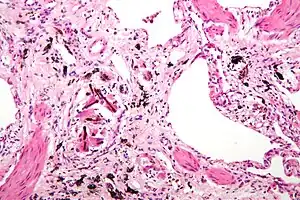

Asbestosis is the scarring of lung tissue (beginning around terminal bronchioles and alveolar ducts and extending into the alveolar walls) resulting from the inhalation of asbestos fibers. There are two types of fibers: amphibole (thin and straight) and serpentine (curly). All forms of asbestos fibers are responsible for human disease as they are able to penetrate deeply into the lungs. When such fibers reach the alveoli (air sacs) in the lung, where oxygen is transferred into the blood, the foreign bodies (asbestos fibers) cause the activation of the lungs' local immune system and provoke an inflammatory reaction dominated by lung macrophages that respond to chemotactic factors activated by the fibers.[19] This inflammatory reaction can be described as chronic rather than acute, with a slow ongoing progression of the immune system attempting to eliminate the foreign fibers. Macrophages phagocytose (ingest) the fibers and stimulate fibroblasts to deposit connective tissue. Due to the asbestos fibers' natural resistance to digestion, some macrophages are killed and others release inflammatory chemical signals, attracting further lung macrophages and fibrolastic cells that synthesize fibrous scar tissue, which eventually becomes diffuse and can progress in heavily exposed individuals. This tissue can be seen microscopically soon after exposure in animal models. Some asbestos fibers become layered by an iron-containing proteinaceous material (ferruginous body) in cases of heavy exposure where about 10% of the fibers become coated. Most inhaled asbestos fibers remain uncoated. About 20% of the inhaled fibers are transported by cytoskeletal components of the alveolar epithelium to the interstitial compartment of the lung where they interact with macrophages and mesenchymal cells. The cytokines, transforming growth factor beta and tumor necrosis factor alpha, appear to play major roles in the development of scarring inasmuch as the process can be blocked in animal models by preventing the expression of the growth factors.[20][21] The result is fibrosis in the interstitial space, thus asbestosis. This fibrotic scarring causes alveolar walls to thicken, which reduces elasticity and gas diffusion, reducing oxygen transfer to the blood as well as the removal of carbon dioxide. This can result in shortness of breath, a common symptom exhibited by individuals with asbestosis.[22]

Extensive fibrosis of pleura and lung parenchyma. -